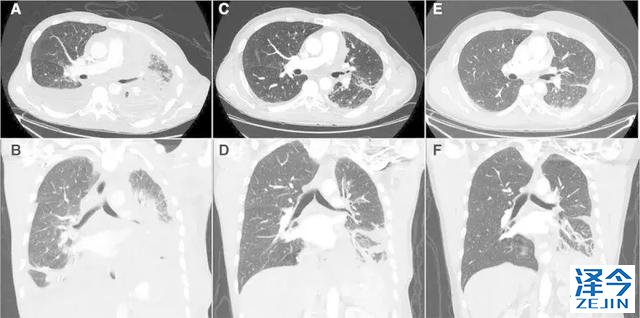

一位77岁的女性患有EPS15-NTRK1 IV期非小细胞肺癌,我们可以看到她的双肺满是病灶,并且出现了肝脏和脑转移,可以说是非常非常晚期了,

既往有乳腺癌史;

既往症状有厌食,乏力,咳嗽,高脂血症;

ECOG 1;

没有接受手术,放疗或化疗。

开始使用larotrectinib 100 mg BID并持续治疗,

第3周期开始:

肺靶病变达到缓解,我们可以明显的看到前后的图像,病灶明显缩小了,

脑转移病变显示缩小了95%!

初始, 2018年6月 3周期 2018年8月